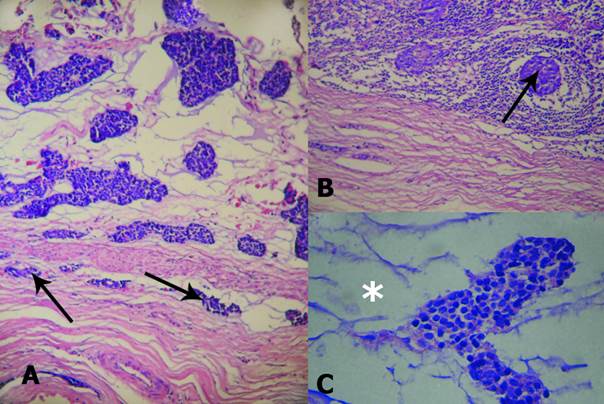

The diagnosis of mixed type basal cell adenocarcinoma was made on the basis of its histological patterns (solid and tubular) and its malignant character, with an aggressive growth with infiltration of the tumor capsule and periparotid fat, perineural invasion and metastasis of a regional lymphoid node (Fig. 2A, B and C).